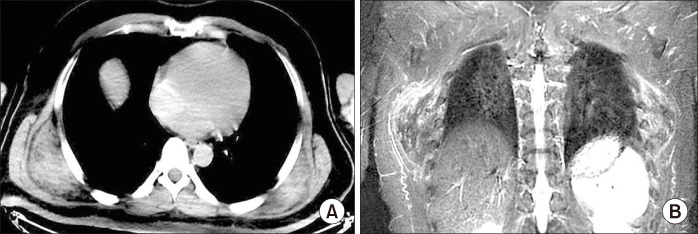

Elastofibroma dorsi (ED) is a rare, benign, slowly growing soft tissue neoplasm characterized by abnormal elastic fiber proliferation. There is a marked female predominance; bilateral presentation occurs in only 10% of cases. ED is usually located in the infra-scapular area, adherent to the posterior chest wall and ribs. Although many theories have been proposed regarding its pathogenesis, the exact cause remains uncertain. Preoperative diagnosis is established based on clinical picture and radiological imaging. We present a case of a 49-year-old man with bilateral ED who complained of back pain and limited shoulder movement, and who underwent simultaneous bilateral surgical removal; histopathological examination confirmed the diagnosis.